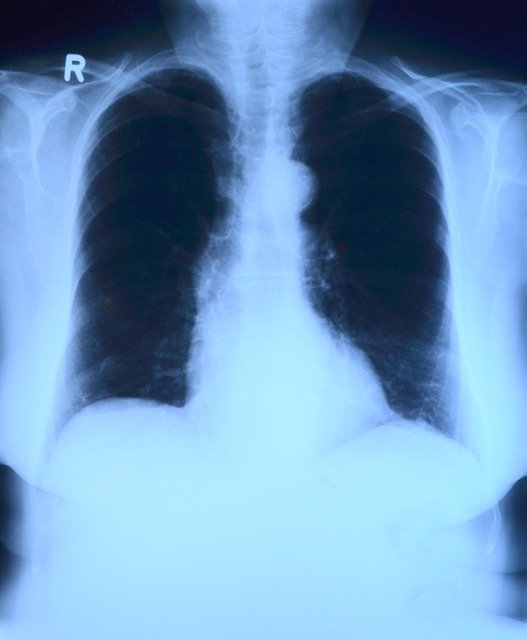

위 사항을 잘 지키더라도 폐암에 걸릴 가능성은 있습니다. 그렇기 때문에 정기적인 건강검진은 필수입니다. 폐암의 고위험군에 속하는 경우 흉부 X-ray촬영에서 이상한 것이 발견된다면 CT촬영과 조직검사를 통해 폐암을 진단할 수 있습니다. 폐암은 조기진단이 중요하기 때문에 정기적으로 검진을 받는 것을 추천드리겠습니다. 오늘은 폐암의 초기 증상에 대해서 알아봤습니다.